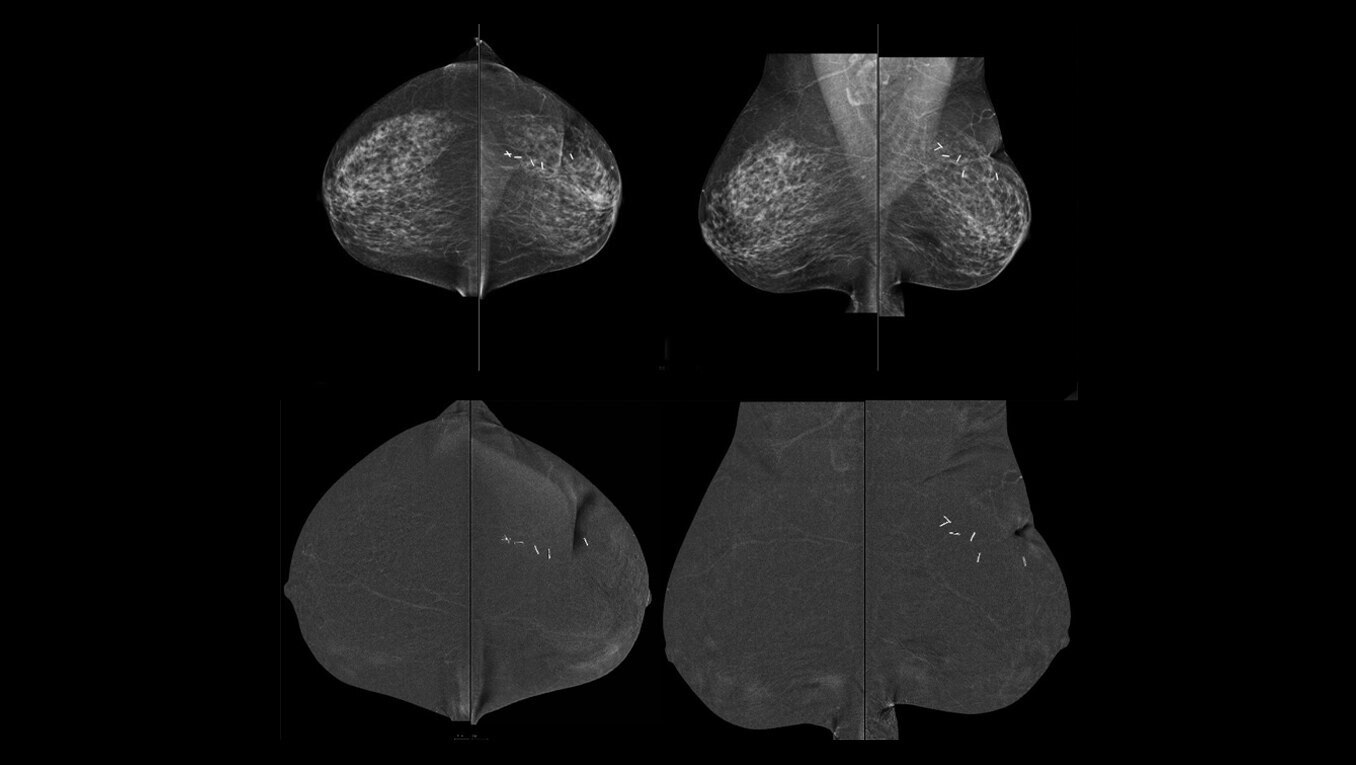

Serena Bright™

Contrast-guided biopsy solution

Utilizes contrast-spectral mammography to clearly target and biopsy lesions without leaving the mammography suite.